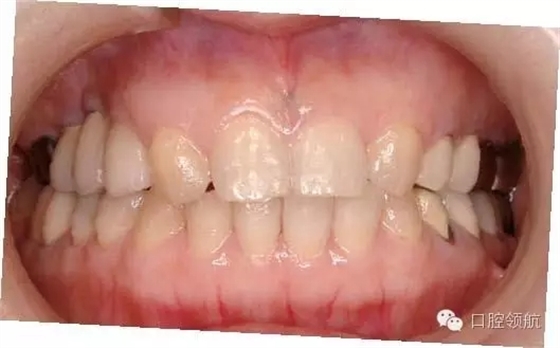

(左上第四顆牙)拔牙后即刻種植,(左上第五、六顆牙)位置用β-TCP做上頜竇內(nèi)提升同期植入種植體的病例(圖1)。

圖2 種植體埋入時的口內(nèi)像

因骨板薄,為獲得初期穩(wěn)定性,種植體植入較淺,導致外部連接系統(tǒng)的愈合帽位于牙槽嵴頂上。